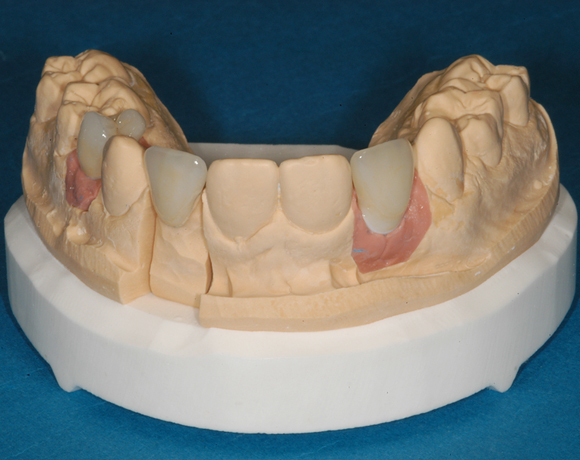

Bei dem letzten Patientenfall lagen Nichtanlagen der Zähne 12, 24, 34, 35, 44, 45 vor. Bei Zahn 12 schimmert das Implantat durch, es war sehr wenig Knochen vorhanden, aber das Ergebnis ist seit acht Jahren konstant gut. Zahn 22 lag als Zapfenzahn vor und wurde mit einem Veneer versorgt.